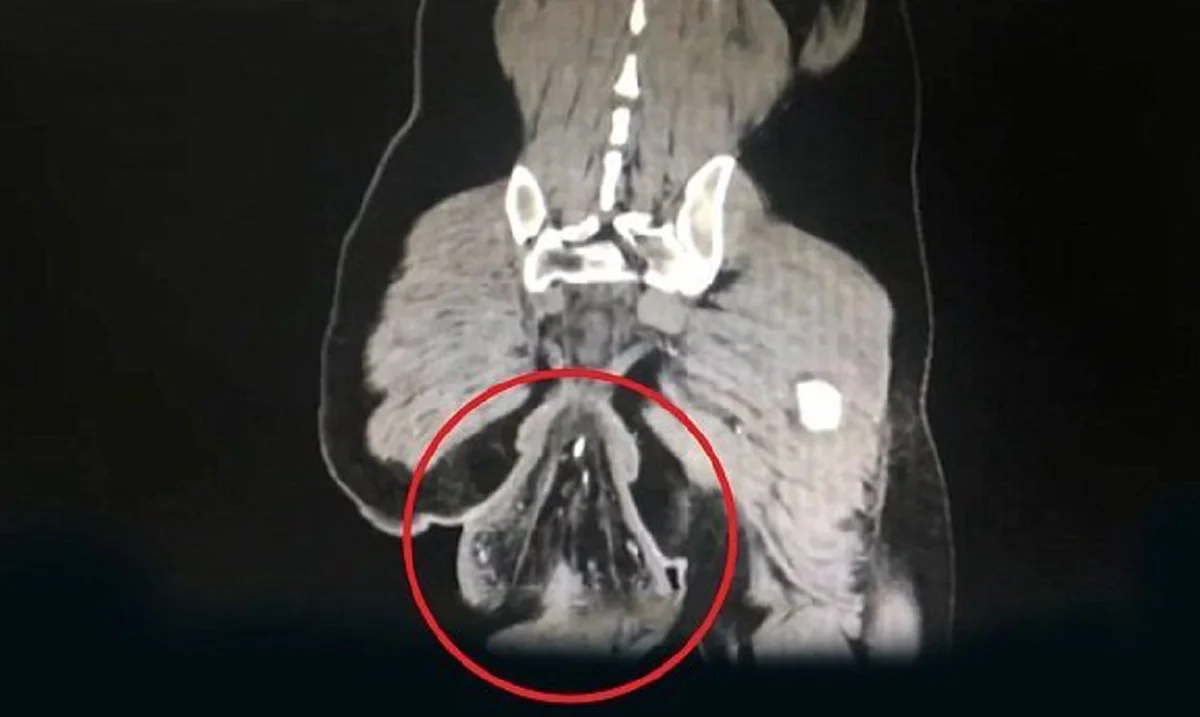

จากภาพเอ็กซ์เรย์จะเห็นได้ว่ามีอวัยวะทรงกลมยุบยื่นออกมาจากรูทวารของชายคนดังกล่าว ก้อนเนื้อที่ผ่าออกมามีขนาดเส้นผ่าศูนย์กลาง 16 เซนติเมตร ก็ฝากเรื่องนี้ไว้เป็นอุทาหรณ์สำหรับใครที่ชอบเอามือถือเข้าไปเล่นในห้องน้ำ เพราะเป็นสิ่งที่ไม่ควรทำ และแม้ว่าตัวชายคนนี้เขาจะมีประวัติเป็นไส้เลื่อนมาตั้งแต่เด็ก แต่การที่เรานั่งชักโครกนานๆ มันจะไปทำให้กระดูกเชิงกรานต้องออกแรงหนักจนล้าได้ และอาจส่งผลให้เกิดโรคริดสีดวงทวารหนักได้อีกด้วย สรุปแล้วเมื่อเราทำธุระเสร็จแล้วเราควรรีบออกจากน้ำจะดีที่สุด ไม่ควรนั่งแช่